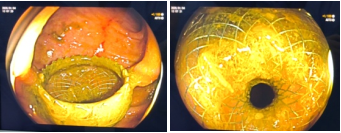

超声引导下释放支架

术中,团队首先通过超声肠镜在乙状结肠探查周围肠管,发现大量肠内容物的明显扩张肠段,考虑为梗阻上游横结肠。为避免再次因肿瘤侵犯导致支架失效,团队选择在远离肿瘤区域的乙状结肠与横结肠进行吻合。在超声内镜引导下,经乙状结肠使用细针穿刺进入横结肠,并在X线实时监视下注入造影剂确认位置,随后成功置入并释放双蘑菇头覆膜金属支架(LAMS支架),实现旷置梗阻肠段、吻合梗阻上下游肠管而打通肠管、恢复排便功能,支架成功置入后瞬间可见较多稀便涌出。术后,团队给予患者精心护理,包括抗感染治疗及静脉营养支持。3天后,患者腹痛、腹胀症状明显缓解,恢复自主排气排便,并已恢复流食。